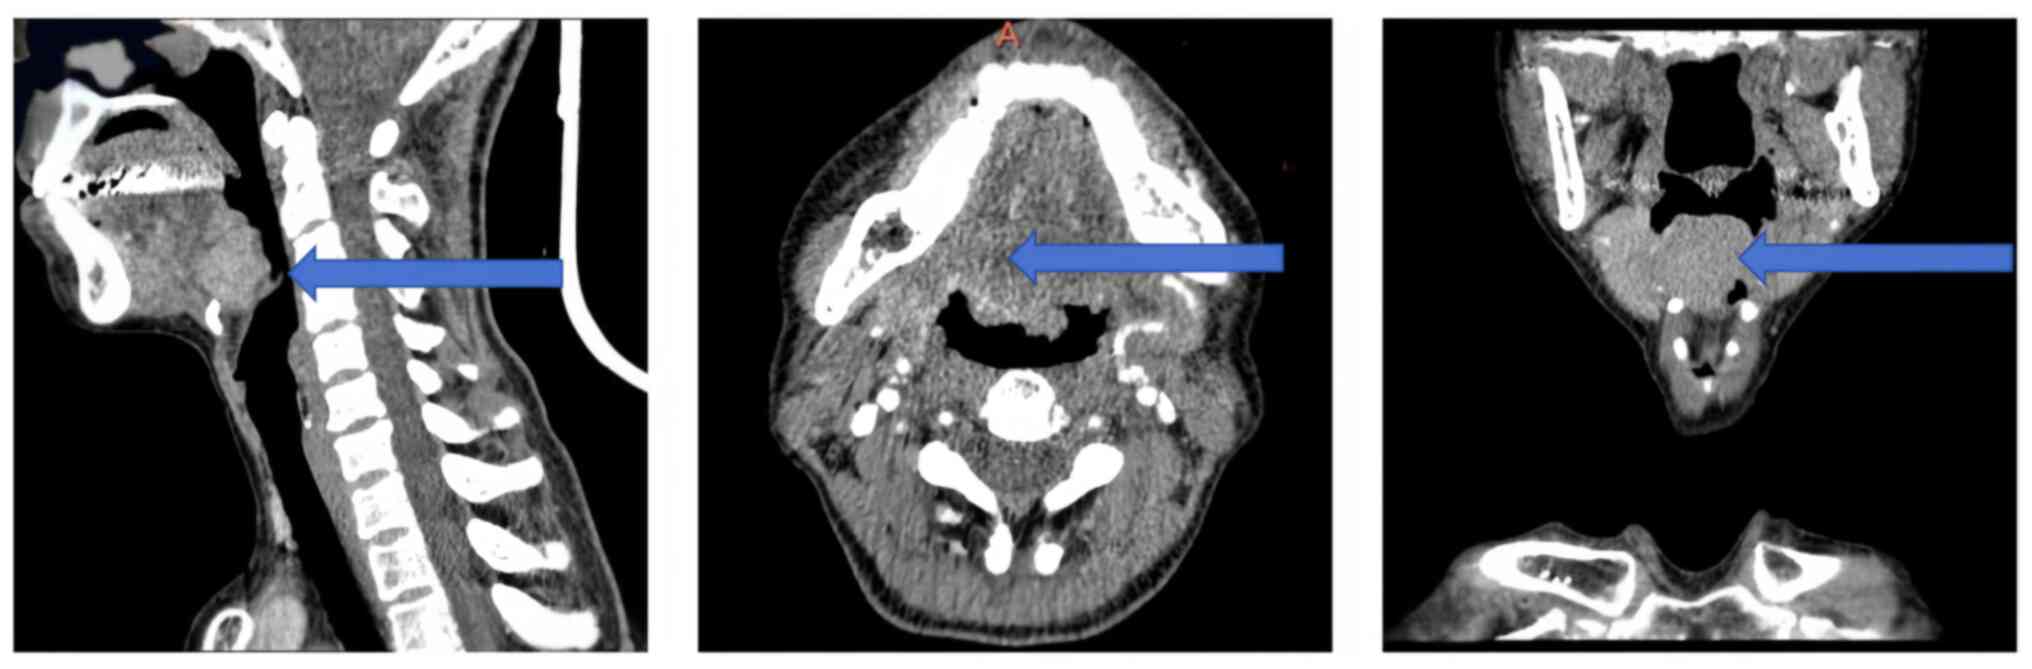

A rare case of hyalinizing clear cell carcinoma of the tongue root: A case report and literature review

The present study describes a rare case of hyalinizing clear cell carcinoma (HCCC) of the tongue root and provides an analysis and review of the relevant literature to improve the understanding of its diagnosis and treatment. Clinical imaging and pathological data from a patient with primary HCCC of the tongue root were summarized, and previously published studies were reviewed through a literature search. The common symptoms, treatment strategies and prognoses reported in the literature were compared. A total of 16 cases of primary HCCC of the tongue were retrieved. Histologically, these cases had tumors characterized by clear cells arranged in sheets, nests and cords within the fibrous interstitium surrounding tumor cells, with round to oval cell nuclei occasionally containing small or inconspicuous nucleoli. Immunohistochemistry showed positive tumor cell staining for cytokeratin (CK)5/6, CK7 and p63, and negative for S‑100, smooth muscle actin and calponin. Clinical symptoms included dysphagia, a painless mass, tongue root ulceration and a foreign body sensation in the throat. Treatment strategies included surgery, radiation therapy, repair and reconstruction, with no local recurrence or metastasis at any follow‑up point. The present findings indicated that HCCC of the salivary glands is an inert malignant tumor, and a good prognosis can be achieved with both surgical resection and radiation therapy.

Figure 2